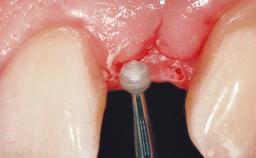

The video demonstrates implant placement using a surgical stent according to the principle of prosthodontically driven implant placement. The deficient ridge is augmented with locally harvested autologous bone chips, a superficial layer of xenogenic DBBM particles and a resorbable collagen membrane. The surgery is completed with a precise, tension-free primary wound closure.